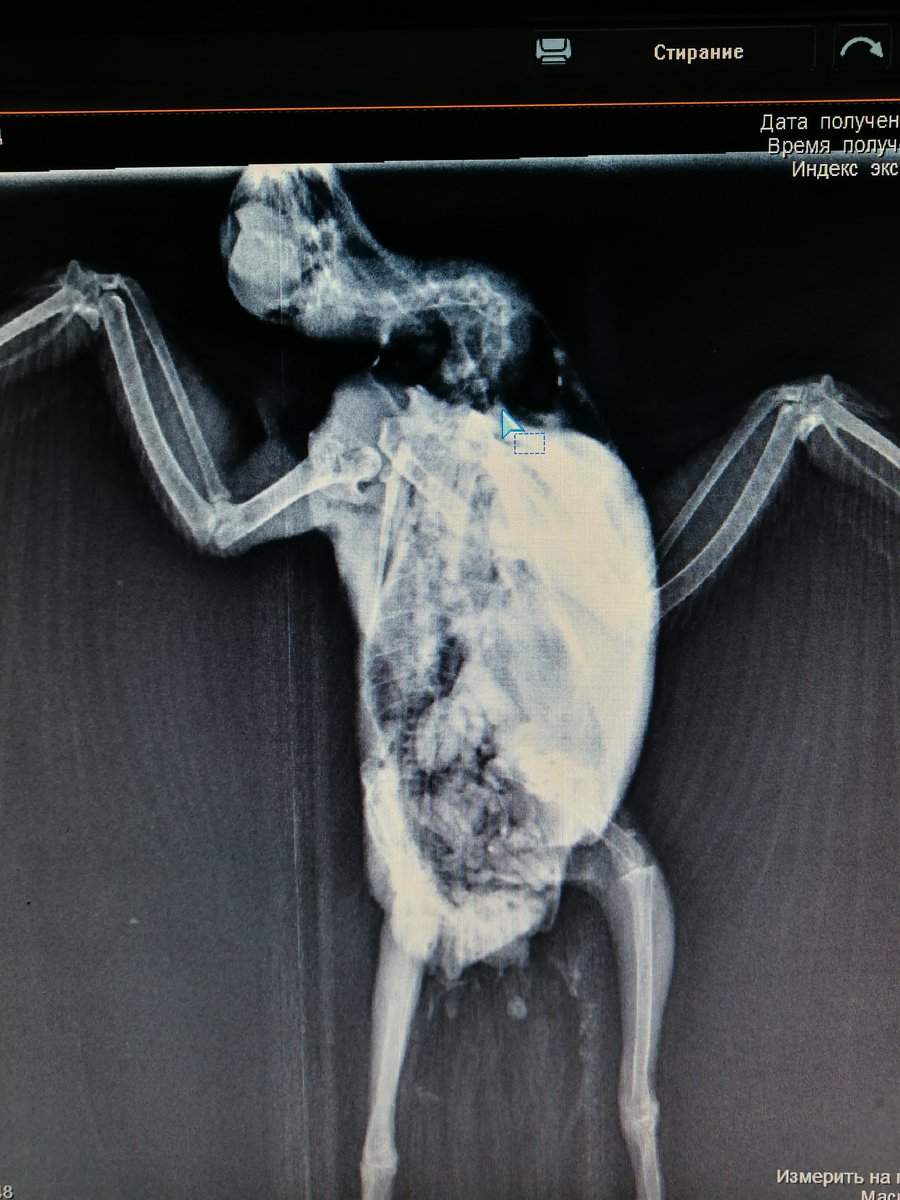

Elena1811 Опубликовано 7 марта, 2020 Автор #113 Опубликовано 7 марта, 2020 Мы старались как могли. Не получается его развернуть полностью из-за левого крыла. Не разворачивается доконца. Боялись сломать

Elena1811 Опубликовано 7 марта, 2020 Автор #115 Опубликовано 7 марта, 2020 5 минут назад, маленький принц сказал: позвал в тему Зосю Спасибо. Будем ждать. И надеюсь снимки читабельны

Elena1811 Опубликовано 7 марта, 2020 Автор #116 Опубликовано 7 марта, 2020 Нам их дополнительно скинули на флэшку

Zosia Опубликовано 7 марта, 2020 #124 Опубликовано 7 марта, 2020 Если есть файлы на флешке- то мне на почту киньте. Т.к. в переснятом виде снимки нечитабельны. zofia68@mail.ru

Elena1811 Опубликовано 11 марта, 2020 Автор #130 Опубликовано 11 марта, 2020 Получила ответ от Зофии. Нужны разъяснения. И некоторые препараты я не могу купить Вот что пишет Зофия: Ну, отличить голубя от голубки я по фото не смогу. Хотя ИМЪО мне видится голубка. И те новообразования в брюшной полости (которые могцт передавливать нервные окончания, идущие к лапкам)- характерны именно для голубок, у меня даже фото есть гранулем, которые у них «рождаются» вместо яиц. Так что ИМХО- итраконазол в дозе 15 мг/кг каждые 12 чсов, нисиатин в дозе 75 000 ед в сутки на 100 гр веса, преднизолон из арсчета 3 мг/кг в сутки. Первый курс- 21 день. Для прикрытия преднизолона- Деринат капли назальные, принимать орально 4 капли в сутки весь курс. Обязательно гепатовте- 0,2-0,3 мл в сутки. По крылу- ваш снимок не дает возможности оценить фатальность нарушений. Но скорее всего- там уже вряд ли что можно сделать (и по-любому это вопрос-не вопрос жизни). ......... У нас беда с преобретением лекарств, рецепты только лишь на аналгин не нужны..